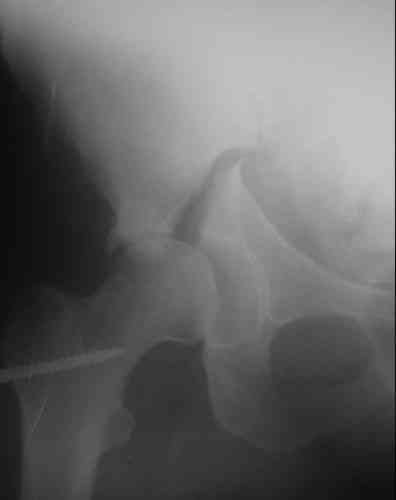

Пациентка 38 лет. В результате ДТП 02.09.06 получила поперечный перелом правой вертлужной впадины, центральный вывих правого бедра, разрыв правого крестцово-подвздошного сустава.

В одной из районных больниц вывих устранен, наложена система вытяжения по оси бедра и за вертельную область. Спустя 2 недели выполнен ВЧКО модулем "таз-бедро". Учитывая возраст пациентки и остаточный диастаз в области свода вертлужной впадины предполагается демонтаж аппарата, открытая репозиция и внутренний МОС вертлужной впадины через внутритазовый доступ.

На показанных снимках повреждение правого КПС не очень заметно...

У меня создалось впечатление( одна из РГ), что участок суставной поверхности нагрузочной зоны вертлужной впадины вдавлен( постарайтесь сделать КТ). Если это подтвердиться, то из внутритазового доступа отрепонировать будет невозможно.